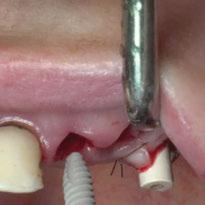

Para ilustrar el proceso, presentamos el caso de una mujer joven diagnosticada de carcinoma adenoide quístico en la región posterior del hemipaladar izquierdo (Figuras 1 y 2). El procedimiento quirúrgico realizado fue una

maxilectomía parcial que incluyó las piezas 24-26 y desde el reborde alveolar hasta la base del cráneo (Figuras 3 y 4). En este caso, la órbita y el globo ocular pudieron ser preservados. La reconstrucción inmediata se realizó mediante un colgajo de músculo temporal homolateral (Figura 5) y el defecto de la fosa temporal fue cubierto mediante una malla de titanio. Posteriormente, la paciente recibió radioterapia (Figuras 6 y 7). 2 años más tarde se diseñó un IS con anclaje en el arbotante nasomaxilar, zona subnasal izquierda

y lo que se pudo preservar del hueso malar. Se añadió una malla sinterizada infraorbitaria para dar volumen a la mejilla y se planificaron dos brazos de conexión que emergieran en las posiciones 24 y 26 de forma subgingival (Figuras 8 y 9). La superficie interna que apoyaba en el hueso era de titanio microrrugoso, y la superficie externa y conectores de titanio pulido y hexágono externo universal (Figuras 10 y 11). La cirugía se hizo bajo anestesia general en infiltración con anestesia local (4% articaína, 1:100.00 epinefrina), levantando el

colgajo cutáneo de la mejilla por vía intraoral, preservando el colgajo temporal para no comunicar con el remanente de la cavidad naso maxilar (Figura 12). Se emplearon 10 tornillos de osteosíntesis de 1,9 mm y la estabilidad primaria obtenida fue excelente (Figura 13)